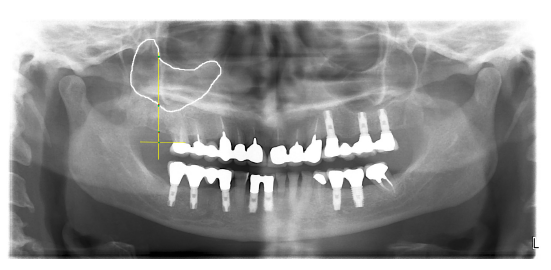

ImageJ software (ImageJ 1.50i, Wayne Rasband National Institutes of Health, USA) was used to measure maxillary sinus sagittal circumference (Fig. 3).

Fig. 3.

Fig. 3.Maxillary sinus sagittal circumference.